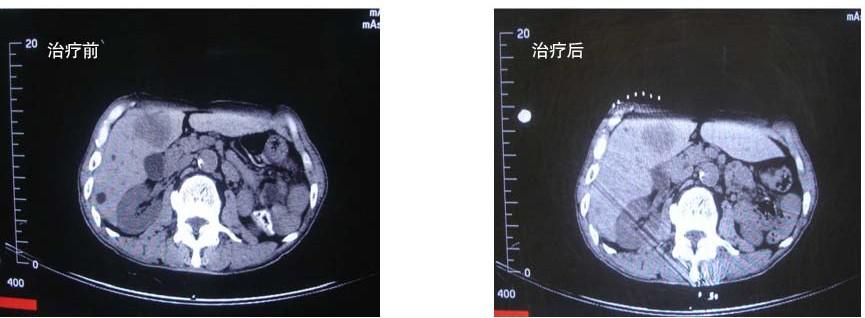

超声检查于肝右前叶胆囊右前方见范围约 4.6 cm×4.2 cm×2.3 cm 的实性低回声团块,边界欠清晰,形态不规则,内回声尚均。CT 检查示肝右叶第五段见类圆形肿块,边界清晰,大小约 5 cm×3 cm,肿块轻中度不均匀强化。

患者入院后行缓释库治疗 2 次。治疗后于 2009 年 3 月 27 日好转出院。于 2009 年4月 19日复查 CT时肿瘤缩小为 4 cm×2.6 cm。后来又经 2 次巩固治疗,肿块控制稳定。

患者治疗前后对比见图 10-6。

图 10-6 刘某治疗前后对比